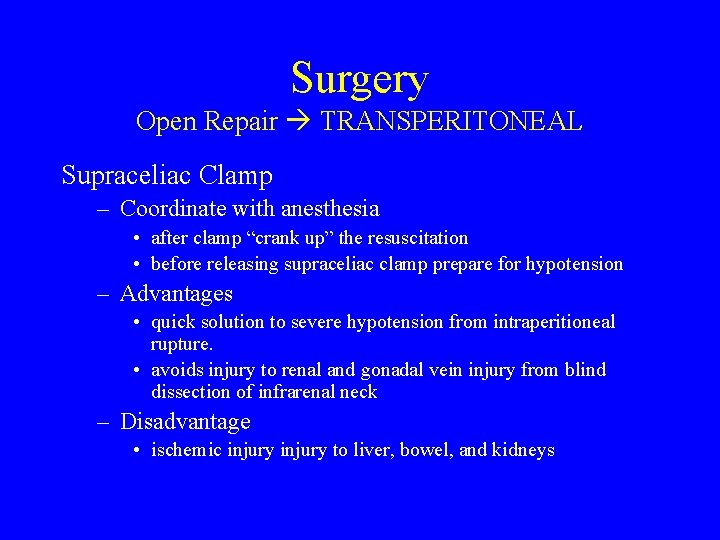

Surgery Open Repair TRANSPERITONEAL • Transperitoneal allows the fastest and easiest approach for Supraceliac clamp • Retract the left lobe of the liver to right to show supraceliac aorta at diaphragm • NG tube identifies esophagus and proximal stomach and retracts to the left • Enter lesser sac by opening gastrohepatic omentum • Aorta is found between crura of diaphragm and is clamped – Can reposition clamp to infrarenal neck of aneurysm once aneurysm is opened – or can make first anastamosis in aneurysm sac and then transfer clamp to graft to reperfuse kidneys and viscera.

Surgery Open Repair TRANSPERITONEAL Supraceliac Clamp – Coordinate with anesthesia • after clamp “crank up” the resuscitation • before releasing supraceliac clamp prepare for hypotension – Advantages • quick solution to severe hypotension from intraperitioneal rupture. • avoids injury to renal and gonadal vein injury from blind dissection of infrarenal neck – Disadvantage • ischemic injury to liver, bowel, and kidneys